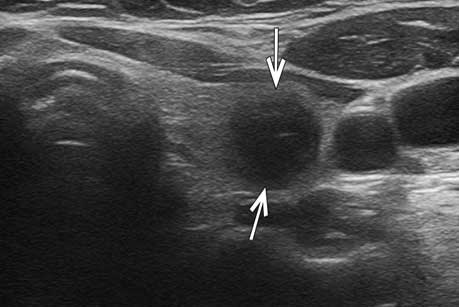

甲状腺左叶实性结节,形态欠不规则,边界尚清,局部紧邻后方被膜,结节内部可见强回声钙

超声造影全程结节无增强